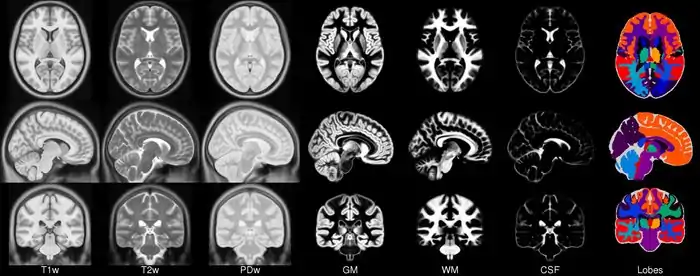

In 2001, within the context of the ICBM project (19) a concerted effort was undertaken by three sites (MNI, UCLA, RIC) to collect a set of full- brain volumetric images from a normative population specifically for the purposes of generating a model. 152 new subjects were scanned using T1, T2 and PD sequences as the MNI’s part of the ICBM project using a specific protocol (27). These images were acquired at a higher resolution than the original average 305 data and exhibit improved contrast due predominately to advances in imaging technology. Each individual was linearly registered to the average 305 and a new model was formed. In total, three models were created at the MNI, the ICBM152_T1, ICBM152_T2 and ICBM152_PD from 152 normal subjects. This resulting model is now known as the ICBM152 (although the model itself has not been published). One advantage of this model is that it exhibits better contrast and better definition of the top of the brain and the bottom of the cerebellum due to the increased coverage during acquisition.

The entirely automatic analysis pipeline of this data also included grey/white matter segmentation via spatial priors (41). The averaged results of these segmentations formed the first MNI parametric maps of grey and white matter. The maps were never made publicly available in isolation but have formed parts of other packages for some time including SPM, FSL AIR and as models of grey matter for EEG source location in VARETTA and BRAINWAVE.